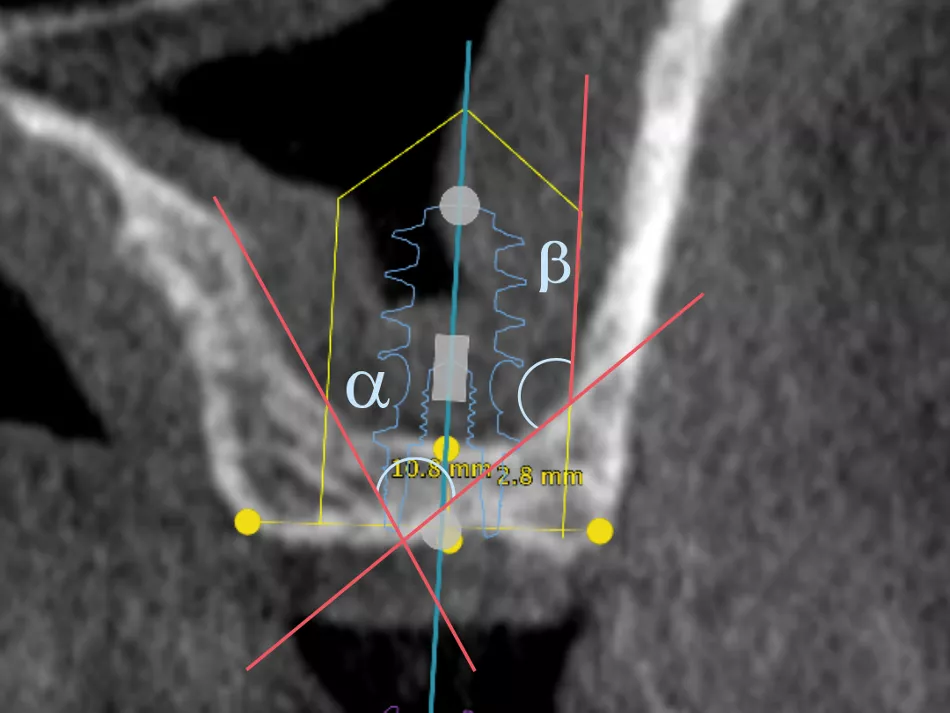

2a. 2b. Pre-operative CBCT scan :

Crestal bone dimensions width 10.8 mm and height: 2.8 mm.

The Alpha angle, formed by the anterior lateral wall of the maxillary sinus and the palatal wall, is favorable at > 60° ​[1]​.

The thickness of the sinus mucosa is favorable > 1.5 mm, indicating a limited risk of perforation. Thickening is not pathological in this patient.

The thickness of the vestibular bone wall is normal, between 1 and 2.5 mm. No intra-sinus septum.

The Beta angle, formed by the palatal wall of the maxillary sinus and the inter-sinus-nasal septum, is on the other hand very closed, which may entail risks in the detachment of the mucosa in this area.